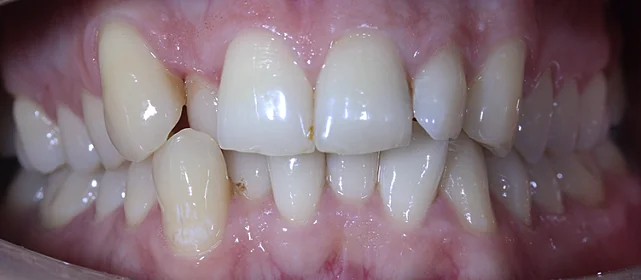

Обе челюсти сужены — зубам не хватало места, они стояли скученно на верхней и нижней челюсти. Нарушена кривая смыкания — жевательные зубы были на разной высоте.

Проблема: Пациентка живёт за рубежом и обратилась с жалобами на неровные зубы. При осмотре обнаружили сужение обеих челюстей, скученность на верхней и нижней, а также деформацию кривой смыкания — жевательные зубы стояли на разной высоте, из-за чего нагрузка при еде распределялась неравномерно. Дополнительная сложность — пациентка не могла приезжать на визиты часто.